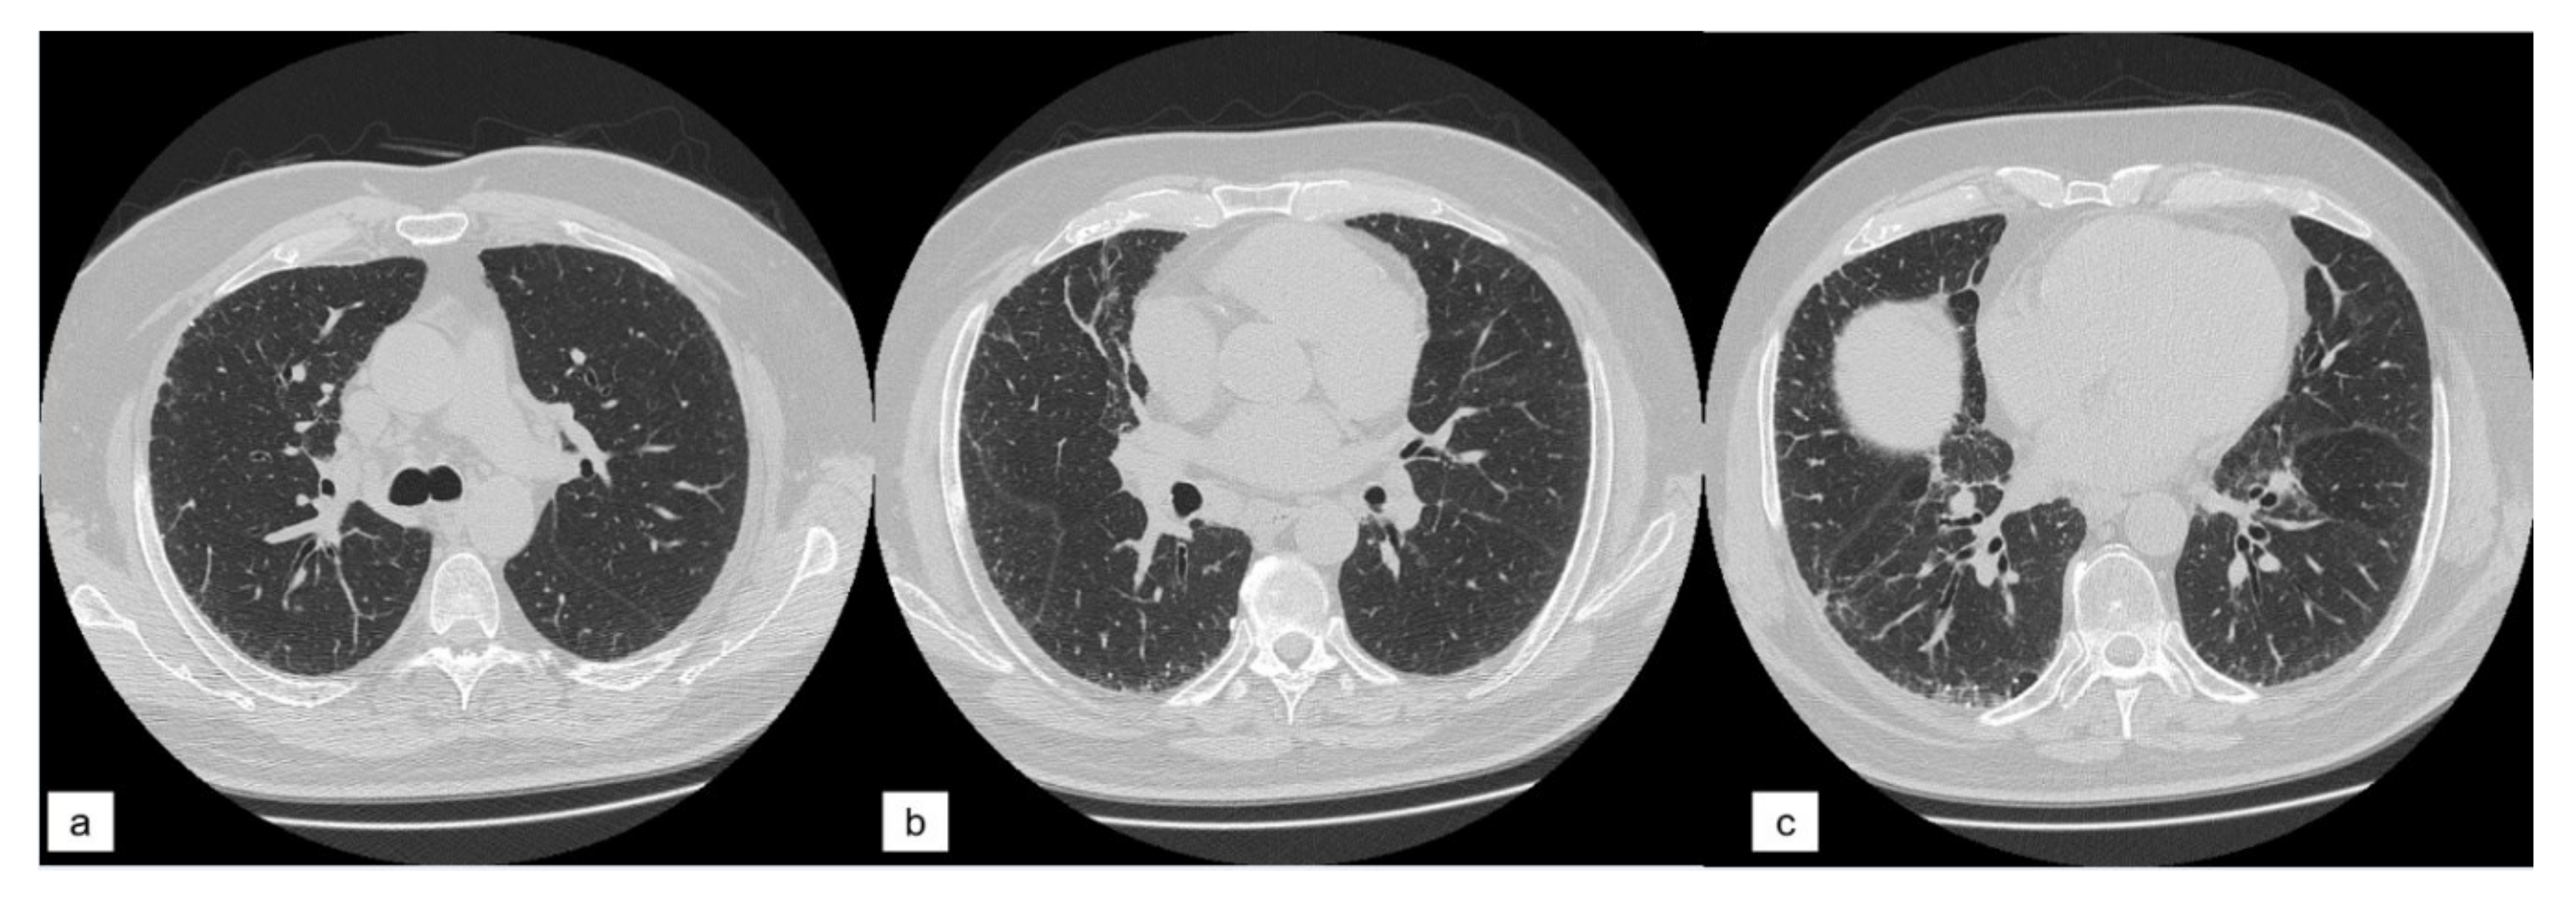

Quantitative HRCT analysis has been proposed to characterize disease prognosis and stratify patients [6], while Oda, in 2014 [7], proposed the visual score, assessed on HRCT images using a semiquantitative analysis. This visual score may be considered a marker for monitoring disease evolution. In addition to this quantitative approach, several papers have recently investigated biological, clinical, and radiological markers that influence disease behavior [8,9,10]. In this regard, the influence of pulmonary ossification in disease evolution nowadays is still uncertain. Diffuse pulmonary ossification (DPO) is a rare form of ILD and it is less frequent in patients without a background of lung disease. DPO is characterized by small tiny calcifications, with or without bone marrow, located in the subpleural regions of lungs. Among the two forms (dendriform and nodular) described in literature, the dendriform DPO is more often associated with chronic obstructive lung disease and interstitial fibrosis (Figure 1) (Table 1) [11,12,13]. The presence of DPO can help the diagnose of Usual Interstitial Pneumonia (UIP) and it can be considered as an ancillary finding of fibrosis [14,15].

Figure 1. Two examples of dendriform ossification (orange circles), localized in subpleural regions.